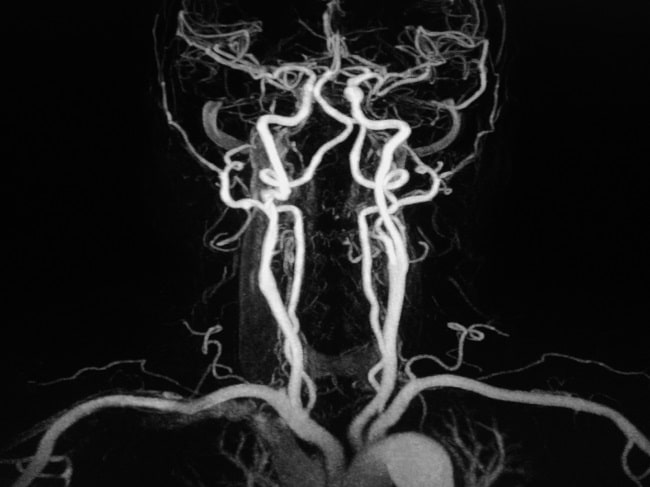

Angiografi serebral atau DSA serebral (digital subtraction angiography) saat ini merupakan pemeriksaan baku emas untuk malformasi arteri dan vena serebral, seperti stroke dan aneurisma serebral. Selain itu, DSA dapat digunakan untuk mengidentifikasi kelainan pembuluh darah spinal, misalnya stenosis arteri vertebral.[1-3]

DSA serebral merupakan prosedur medis invasif, untuk mengevaluasi sistem vaskuler serebral. DSA dapat membantu mendiagnosis kondisi sistem arteri dan vena serebral, kegawatan sistem pembuluh darah serebral, dan sistem kolateral dari pembuluh darah serebral.[1,2]

Penggunaan kata subtraction memiliki arti penggunaan sistem digital untuk menghilangkan struktur radiopak seperti tulang, sehingga didapatkan gambaran yang lebih presisi pada sistem pembuluh darah. DSA serebral dapat dilakukan pada rumah sakit yang memiliki fasilitas kateterisasi. Prosedur ini menggunakan kateter, wire, dan zat kontras dengan pencitraan oleh mesin angiografi yang memiliki software DSA.[1,2]